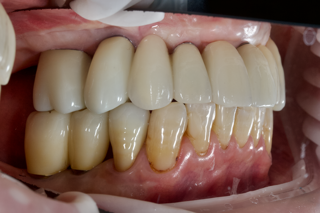

左側 before

左側 after